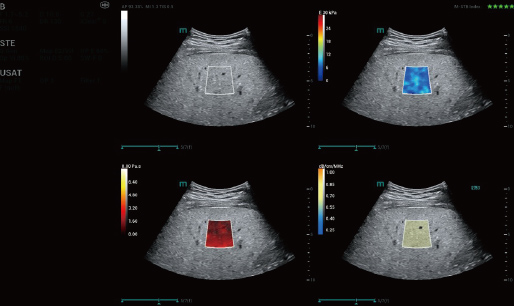

STVi maakt de kwantitatieve evaluatie van weefselviscositeit mogelijk en biedt realtime, multi-parametrische beeldvorming. Dit maakt een bredere benadering mogelijk van beeldvormingsdiagnose en kwantitatieve analyse van chronische leverziekten, borstlaesies en andere aandoeningen.

Dubbele kwantitatieve co?ffici?nten

Beoordeling van chronische leveraandoeningen